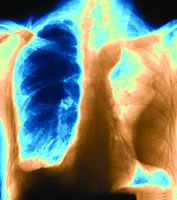

2.X線檢查因胸膜腔積液的量和部位不同表現各異。